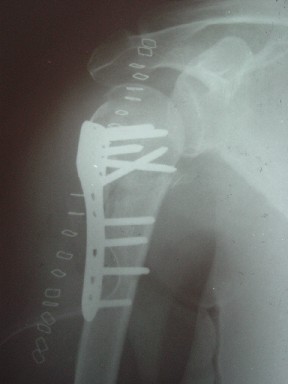

Уважаемые коллеги

сделать закрытую репозицию с помощью ЭОПа совсем не сложно, после этого еще проще провести 3-6 спиц и получить красивую рентгенограмму. Есть только небольшая проблема это ROTATOR CUFF. Для плечевого сустава только костное восстановление не достаточно. для функции плечевого сустава нужны вращатели.

Давайте представим себе состояние манжетки вращателей после вывиха плеча, а еще и с отрывным переломом бугров. Головка может и прирастет, еесли не будет аваскулярного некроза, но хорошего функционального результата не ждите.

Висеть будет красиво. У людей физически активного периода жизни нужно открыть, восстановить костную анатомию и восстановить сухожильный аппарат.

В этом плане Locking plate очень хороша так как позволяет начать движения сразу после операции.

Клинические снимки - 3 недели после операции

с уважением М. Беренштейн